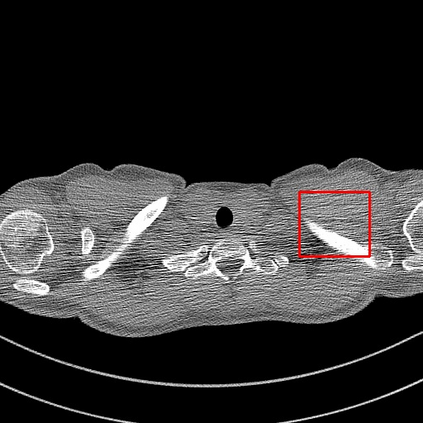

Low-Dose Computed Tomography (LDCT) technique, which reduces the radiation harm to human bodies, is now attracting increasing interest in the medical imaging field. As the image quality is degraded by low dose radiation, LDCT exams require specialized reconstruction methods or denoising algorithms. However, most of the recent effective methods overlook the inner-structure of the original projection data (sinogram) which limits their denoising ability. The inner-structure of the sinogram represents special characteristics of the data in the sinogram domain. By maintaining this structure while denoising, the noise can be obviously restrained. Therefore, we propose an LDCT denoising network namely Sinogram Inner-Structure Transformer (SIST) to reduce the noise by utilizing the inner-structure in the sinogram domain. Specifically, we study the CT imaging mechanism and statistical characteristics of sinogram to design the sinogram inner-structure loss including the global and local inner-structure for restoring high-quality CT images. Besides, we propose a sinogram transformer module to better extract sinogram features. The transformer architecture using a self-attention mechanism can exploit interrelations between projections of different view angles, which achieves an outstanding performance in sinogram denoising. Furthermore, in order to improve the performance in the image domain, we propose the image reconstruction module to complementarily denoise both in the sinogram and image domain.